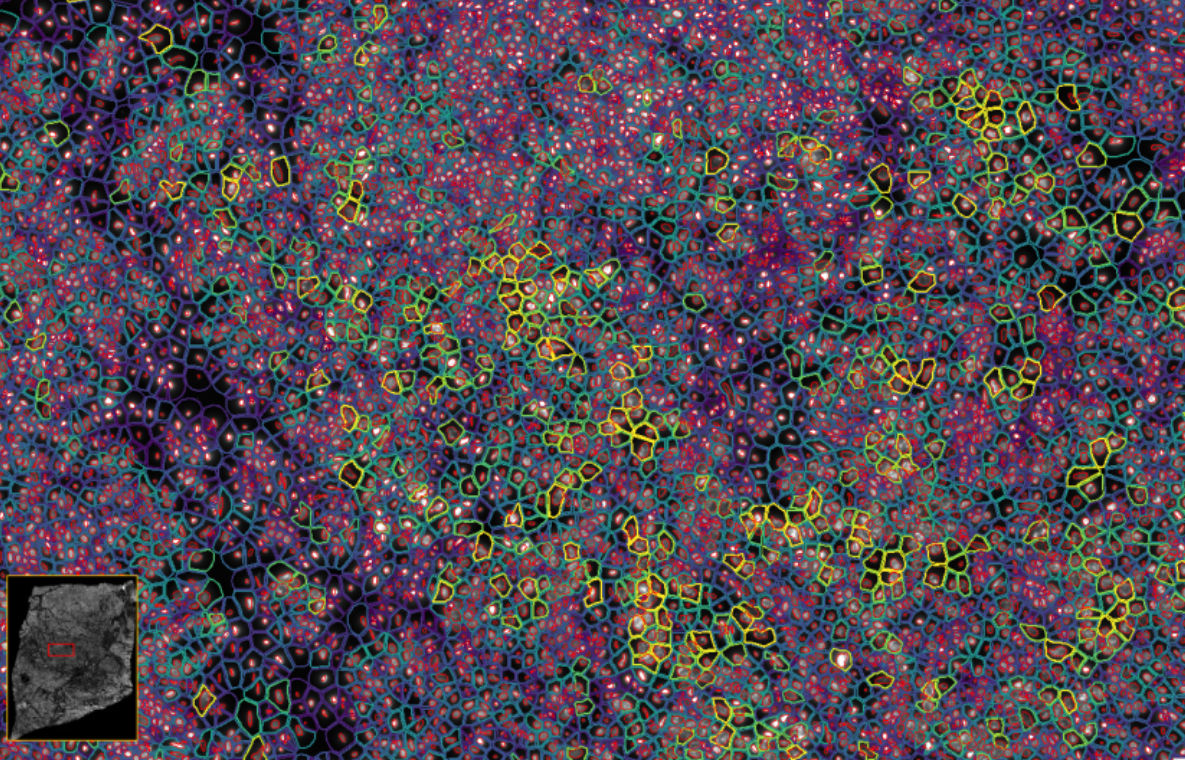

ͼ2£ºXeniumÊý¾Ý¸ÅÀÀ

ͼ3£ºXenium½«¹âÑ§ÌØÕ÷½âÂëΪת¼±¾±í´ï£¬ÊÕÂÞ²¢ÐγÉͼÏñ

ͼ4-1£ºÊ¹ÓÃDAPI¶Ôϸ°ûºËȾɫ£¬ÍŽáÉî¶ÈѧϰҪÁìÍÆ¶ÏÍêÕûµÄϸ°û½çÏß

ͼ4-2£ºÊ¹ÓÃDAPI¶Ôϸ°ûºËȾɫ£¬ÍŽáÉî¶ÈѧϰҪÁìÍÆ¶ÏÍêÕûµÄϸ°û½çÏß